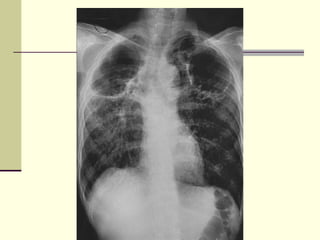

Cavitating Pneumonia   1. Staph  2. Strep 3. TB  4. Gram negative (Klebsiella)

Staph